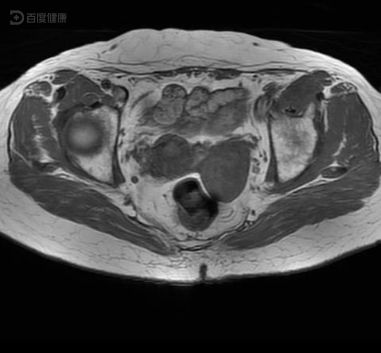

患者入住我科后立即予完善常规妇科入院检查等,MRI检查结果回报“左侧附件区发现肿块,考虑卵巢癌。”患者目前经MRI检查明确卵巢肿瘤,结合恶病质表现,目前考虑诊断为卵巢癌,建议患者立即进行手术,有助于改善疾病预后及制定后续的治疗方案,患者同意进行手术,遂立即给予左侧卵巢根治性手术。术后送检病理,结果回报提示卵巢癌,根据目前的综合情况,诊断患者疾病为卵巢癌。遂给予术后心电监护,血氧饱和度监测,术后给予顺铂联合依托泊苷进行化疗,同时予维生素B12营养神经、氯化钠补液等处理,经手术及术后化疗等辅助治疗后无腹部疼痛,术后手术切口处无红肿、渗液等感染倾向,未见明显手术后遗症,未见明显化疗的相关不良反应,患者持续治疗10天后患者康复出院。

(MRI:左侧附件区发现肿块,考虑卵巢癌。)